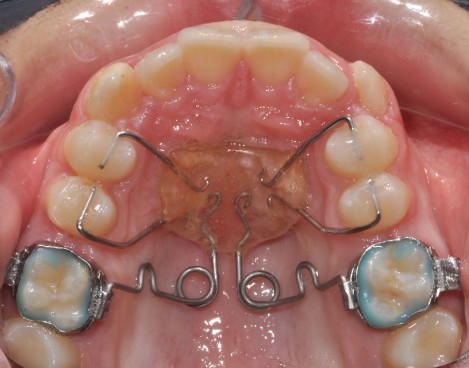

Предимства на методите на лечение с интраоралния фиксиран апарат M-Pendulum

За да се достигне до решение за избор на екстракционно или безекстракционно оротодонтско лечение е необходимо да се съобразим с недостига на място в зъбната дъга и продължителността на лечението. За това си поставихме за цел да съпоставим тези параметри.

Клинични аспекти при прилагане на апарата Pendulum в смесено съзъбие

В тази статия си поставяме за цел да разискваме от клинична гледна точка позитивите и негативите при ползване на апарата Pendulum в смесено съзъбие. Ще разгледаме становищата за работа с апарата в случаите, когато са включени временните молари като опорна зона. Ще дадем какви са според нас клиничните предпоставки и индикации за използването на Pendulum в смесено съзъбие.